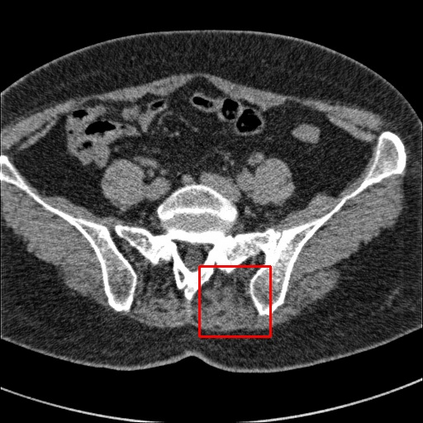

Low-Dose Computed Tomography (LDCT) technique, which reduces the radiation harm to human bodies, is now attracting increasing interest in the medical imaging field. As the image quality is degraded by low dose radiation, LDCT exams require specialized reconstruction methods or denoising algorithms. However, most of the recent effective methods overlook the inner-structure of the original projection data (sinogram) which limits their denoising ability. The inner-structure of the sinogram represents special characteristics of the data in the sinogram domain. By maintaining this structure while denoising, the noise can be obviously restrained. Therefore, we propose an LDCT denoising network namely Sinogram Inner-Structure Transformer (SIST) to reduce the noise by utilizing the inner-structure in the sinogram domain. Specifically, we study the CT imaging mechanism and statistical characteristics of sinogram to design the sinogram inner-structure loss including the global and local inner-structure for restoring high-quality CT images. Besides, we propose a sinogram transformer module to better extract sinogram features. The transformer architecture using a self-attention mechanism can exploit interrelations between projections of different view angles, which achieves an outstanding performance in sinogram denoising. Furthermore, in order to improve the performance in the image domain, we propose the image reconstruction module to complementarily denoise both in the sinogram and image domain.